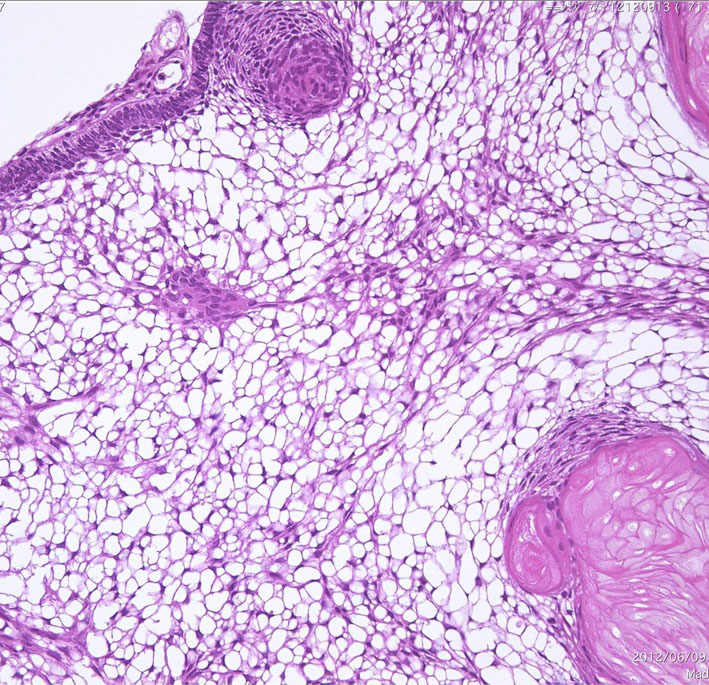

Monomorphous mass of well-differenciated squamous epithelium lacking surface maturation and wet keratin.

摘出した骨化片の病理像です。成熟した骨組織 mature boneです。

adamantinomatous typeです。mature boneの端には破骨巨細胞が多数見られます。

鞍内にあった部分の病理所見です。adamantinoomatous typeで,破骨細胞を伴う強い骨化がみられます。